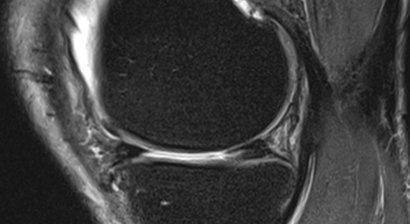

Meniskusriss

Meniskusschäden sind relativ häufig. Sie entstehen in vielen Fällen aufgrund vorbestehender Abnützungserscheinungen, können aber auch rein traumatisch sein. In der Regel ist der Innenmeniskus häufiger von einem Meniskusschaden betroffen als der Außenmeniskus. Ist der Meniskus nur leicht geschädigt (...